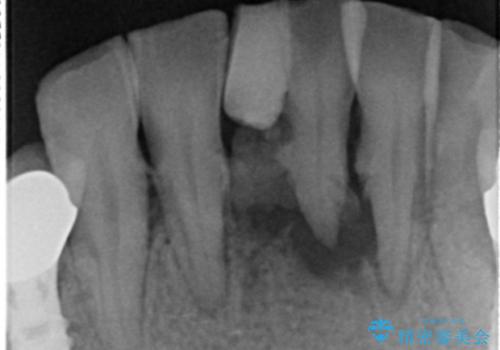

- 上下の前歯が抜けそうだとのことで来院されました。

精査したところ、動揺の著しい上下の前歯は重度の歯周病により保存不可能と判断しました。

歯周病が重度であったため抜歯後の歯肉の陥凹が大きく、GBRや歯肉移植による歯周組織の再建をおすすめしましたが、ご希望されませんでした。